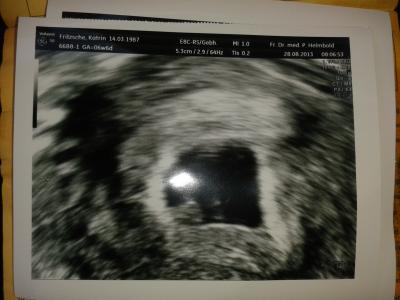

Guten Morgen war gerade beim Fa und was soll ich sagen man konnte das Baby sehen und sogar den Herzschlag. Ich Freu mich so. Danke für das Liebe Daumen drücken.

Bild zu fa termin - Forum für April - Mamis

Das freut mich sehr für dich! Schön dass du auch schon das 1. Bildchen bekommen hast

Ach ist das ein tolles Bild!!!! Weiter so!!!!!

Super toll. Wie weit bist du genau? Ich hab nächste Woche bei 6+0 und hoffe, das man da auch schon was sieht. Bitte versuch das nächste mal dein US Foto so zu bearbeiten, dass man deinen Namen usw. nicht lesen kann. Ist ja hier ein öffentliches Forum, wo jeder alles sehen kann. Nur so als Tip